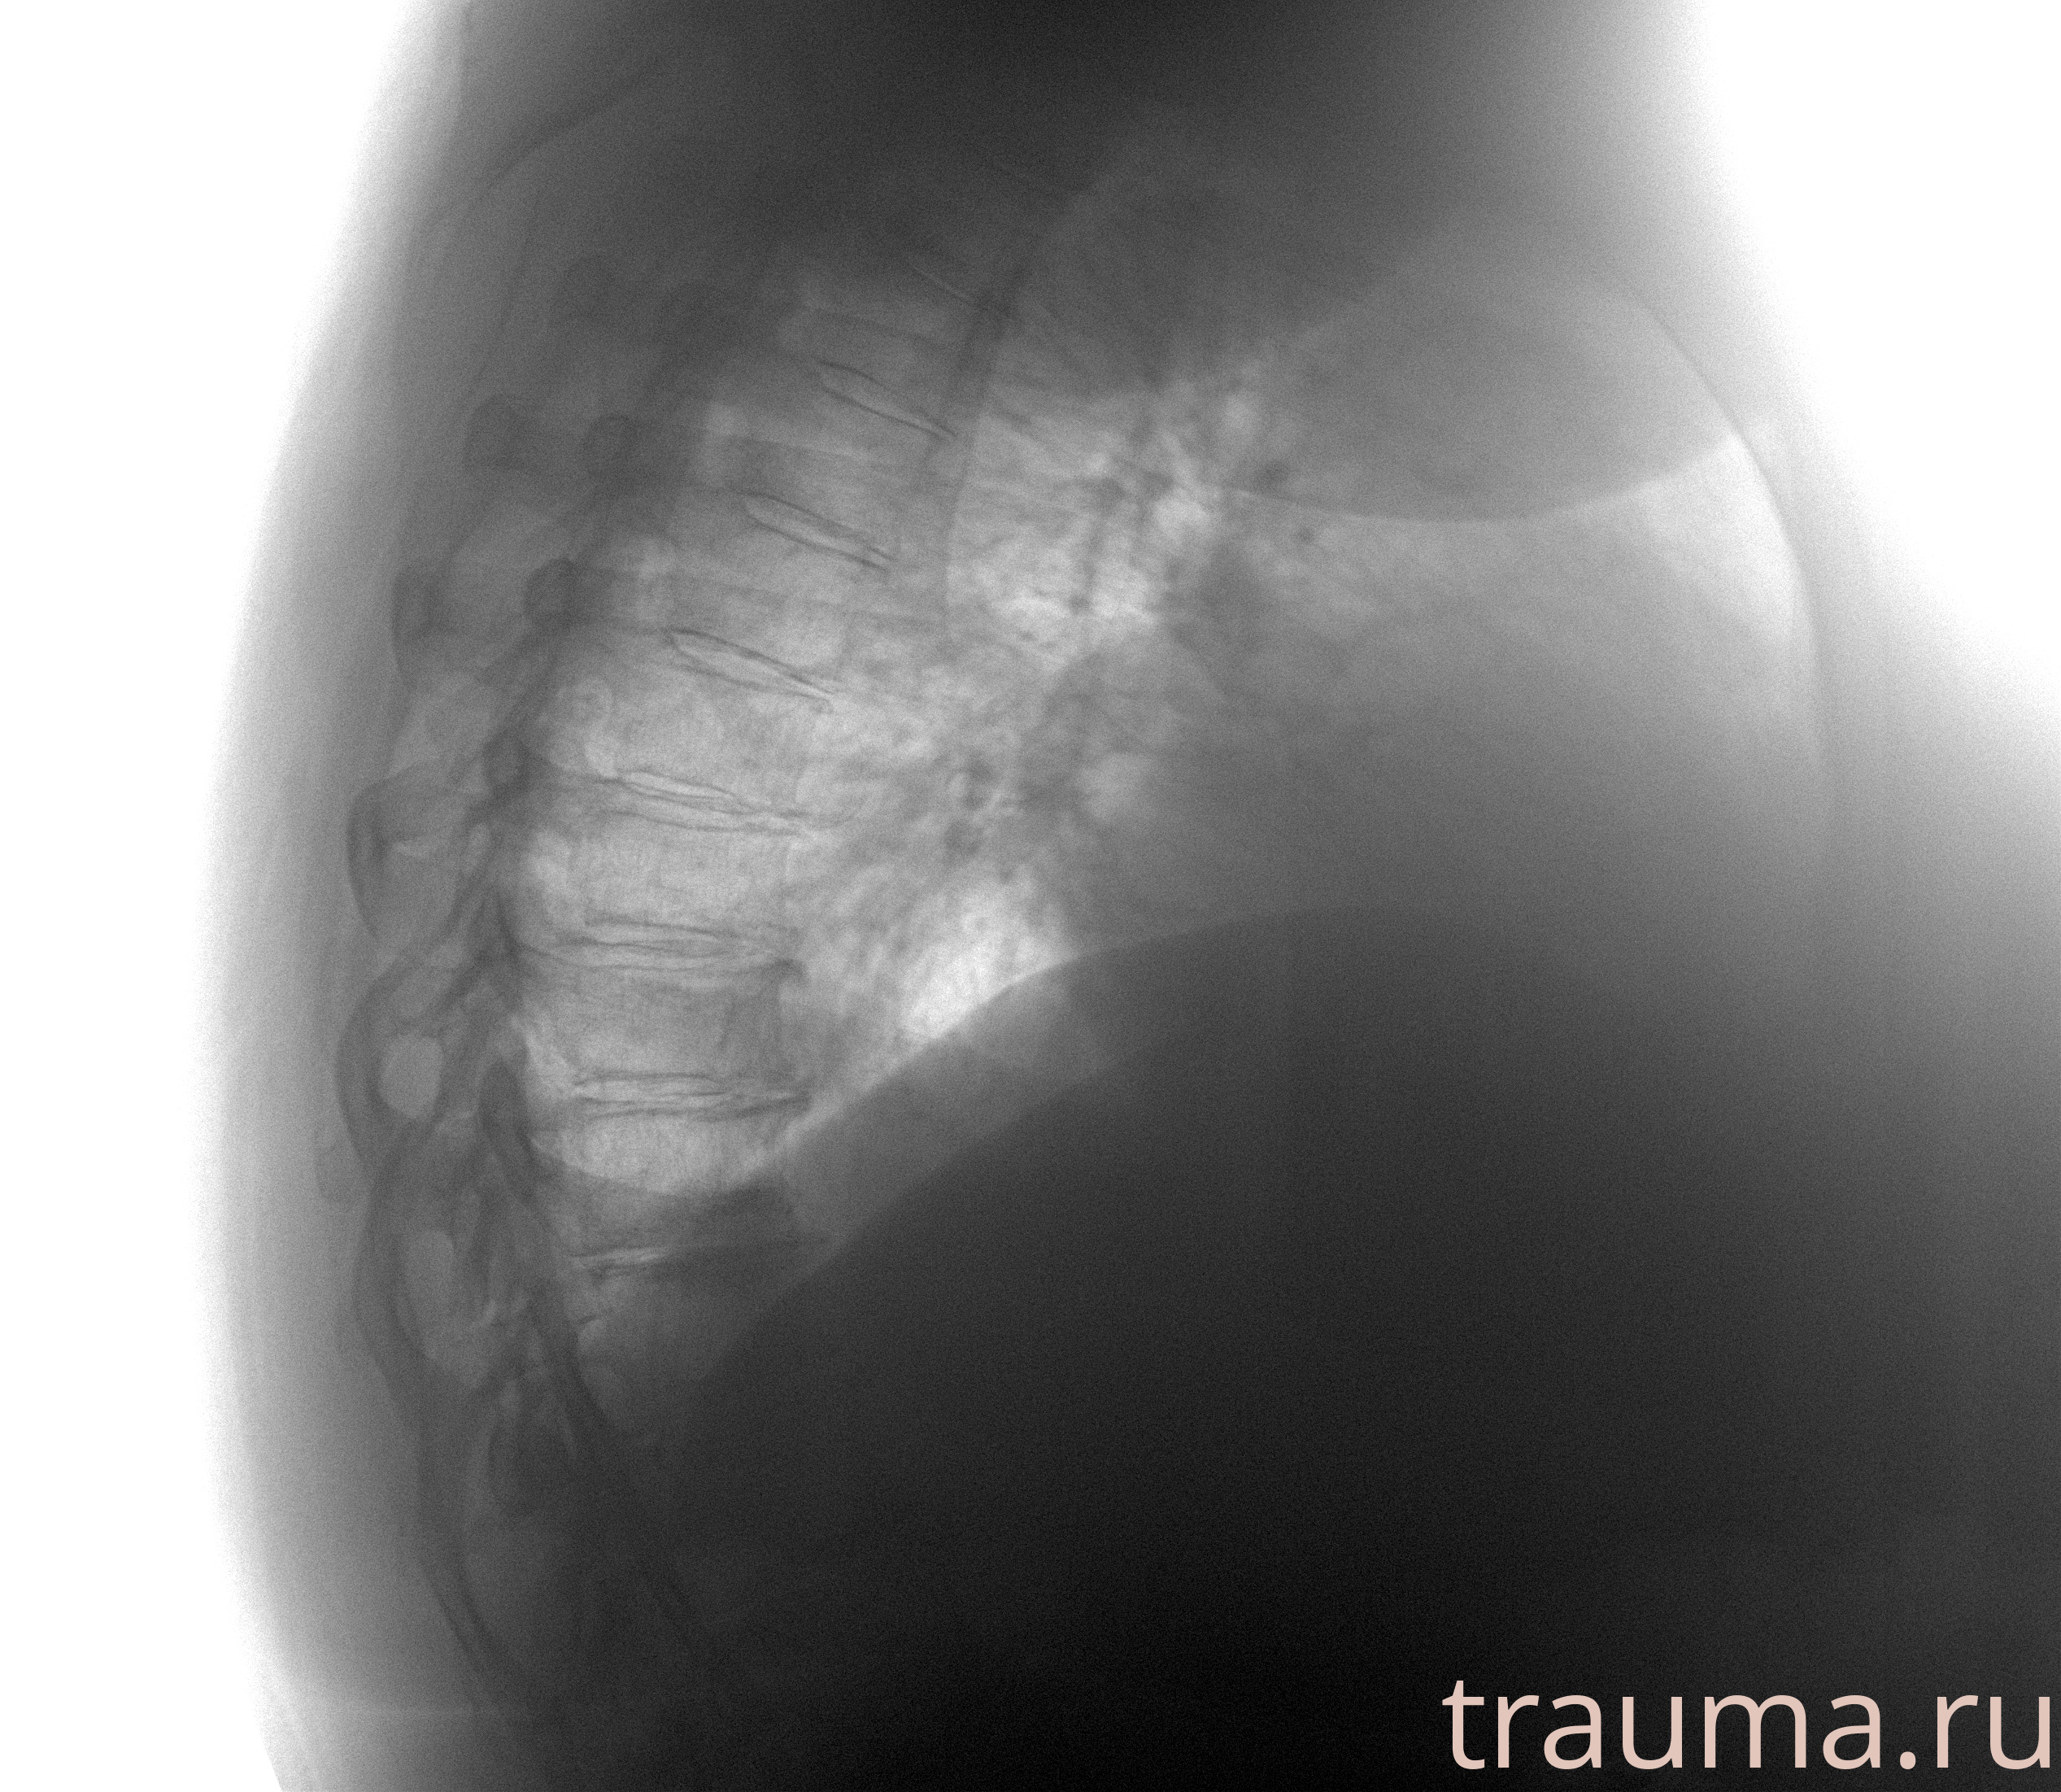

Рентгенограммы

Рентген на дому: по вашему адресу приезжает врач-рентгенолог, травматолог-ортопед с мобильным рентгеновским аппаратом, проводит диагностику травмы или заболевания, делает необходимые рентгенограммы, дает рекомендации по дальнейшему лечению. Получить качественные снимки в домашних условиях возможно благодаря уникальной методике, разработанной МосРентген Центром для института  Склифосовского